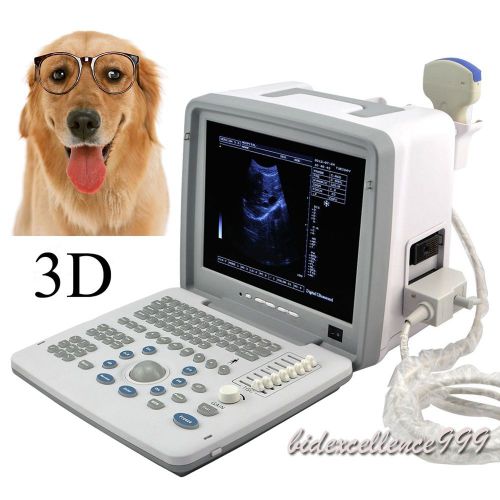

Model | 9000BV |

| Screen Size | 12 Inch | ||

| Image resolution | 800*600 | ||

| Probe | Micro-Convex probe | ||

| Other Choice | Trolley / Video Printer | ||

| Options | Linear / Convex / Rectal |